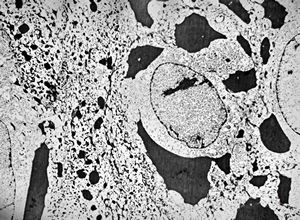

F,64y. | septate junctions between giant multivesicular bodies … uterus, stromal sarcoma

F,64y. | septate junctions between giant multivesicular bodies … uterus, stromal sarcoma

M,51y. | septate junctions between giant multivesicular bodies - lung, necrotizing pneumonia

M,76y. | septate junctions between degraded organelles - mesothelioma